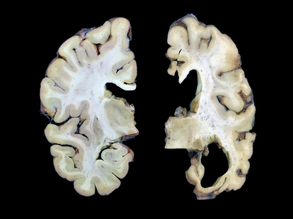

Compare and Contrast